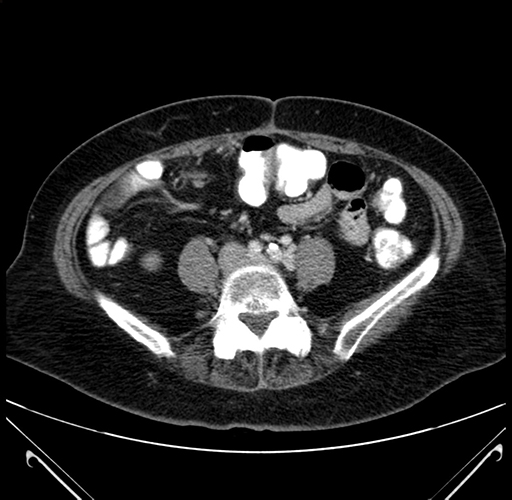

Axial Venous

Based on your CT findings, which issue(s) would give reason for "planned slowing down moment(s)" in this case?

Considering a standard right hepatectomy procedure, what step(s) of the operation would you do differently in this case?